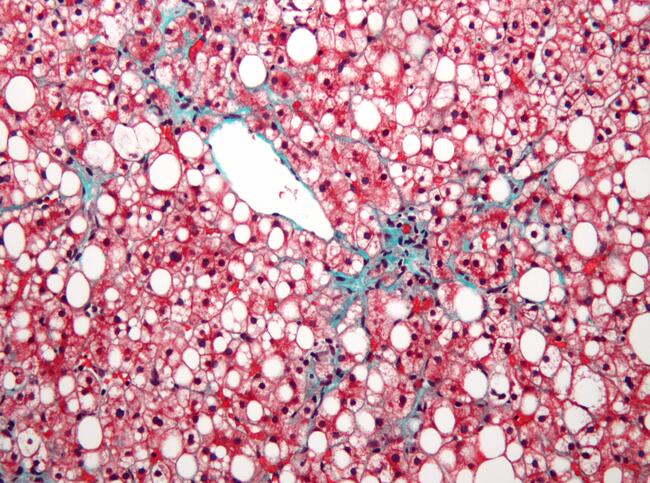

Predicting Mortality and Liver Outcomes in Nonalcoholic Fatty Liver Disease

The Metabolic Vulnerability Index predicts risk of mortality and liver outcomes in patients with nonalcoholic fatty liver disease, according to a study presented at the 2021 American Association for the Study of Liver Diseases meeting.

This study aimed to examine the ability of the Metabolic Vulnerability Index to predict mortality in nonalcoholic fatty liver disease.

Serum samples collected within 6 months of a liver biopsy demonstrating nonalcoholic fatty liver disease were analyzed. The Nonalcoholic Steatohepatitis (NASH) Clinical Research Network system scored histology. The Metabolic Vulnerability Index was scored from 0 to 100 with higher values indicating higher risk for mortality.